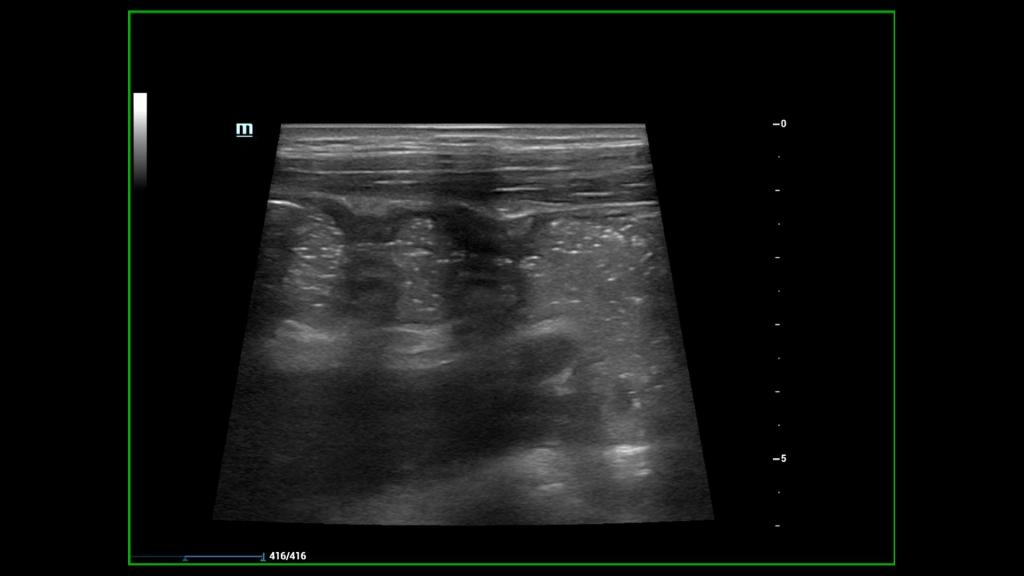

8月22日上午8时许,患儿及家属按约抵达。在超声科儿科亚专业组全体医师的参与下,由超声科刘灿主治医师负责为患儿做了详细的肠道超声检查,对整个肠道每段每节进行测量及记录,为患儿进一步治疗提供真实可靠的超声数据,解除了患儿家长的后顾之忧,患儿本人及家属十分感激,展现出灿烂的笑容。

随着医学水平不断发展,CD的治疗目标已经从症状缓解转变为黏膜愈合。将“全壁愈合”作为CD更深层次的治疗目标。CD “全壁愈合”可以通过磁共振小肠造影 (MRE)、计算机断层扫描 (CT) 和肠道超声 (IUS)进行评估。肠道超声 (IUS)可以检测CD疾病活动、病变范围和并发症,具有非侵入、无创无辐射、易于重复且成本低的优点,尤其适用于小儿。因此,将肠道超声作为判断CD“全壁愈合”的标准,逐渐受到越来越多的关注。